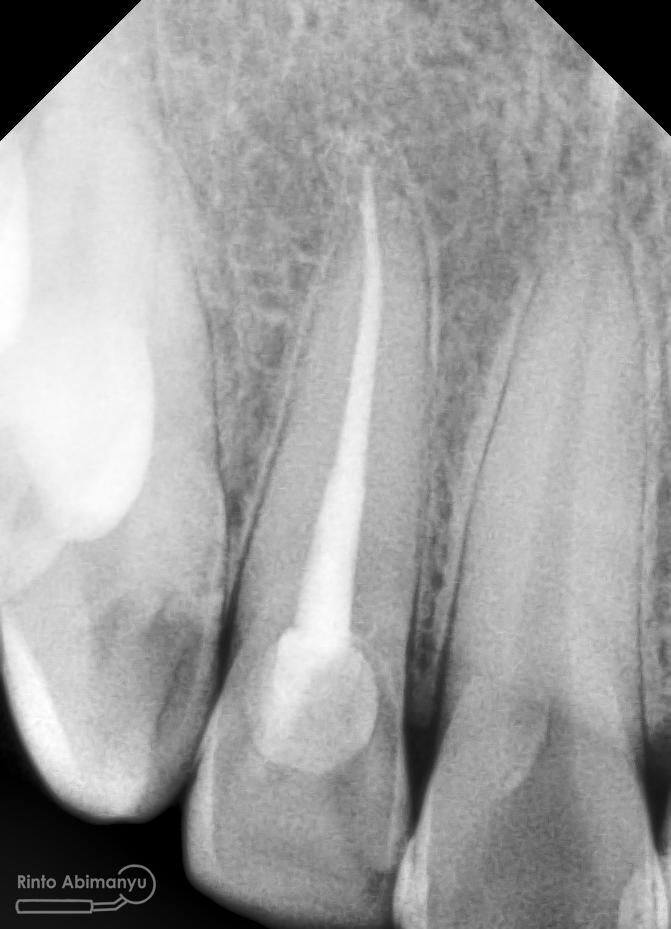

Oo iya tidak lupa juga dilakukan foto ronsen setelah pemasangan crown…

Foto radiografis akhir

Dari foto ronsen terlihat gambaran yang “indah” dari mulai pengisian saluran akar yang rapat dan padat serta gambaran sementasi mahkota yang terlihat homogen….